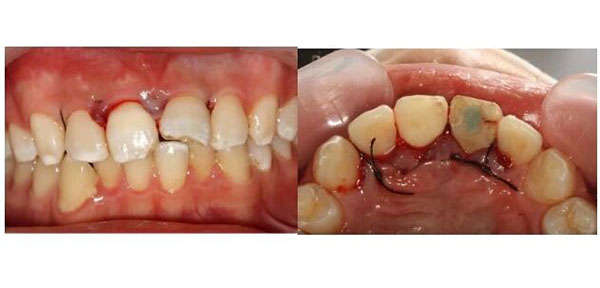

术后1周拆线,伤口长得不错。

术后2周,完成冠部的充填修复。

经过口腔检查,周伟伟看到,两颗门牙中那颗受伤更重的,确实是复杂冠根折:就是从牙冠到牙根都裂开了,牙神经也暴露了;而且折断的地方很深,一直延伸到牙龈下面。

先完成根管治疗,把牙齿内部清理干净。然后,在手术显微镜下,翻开牙龈,暴露出深藏在牙槽骨里的断端,用纤维桩像“钢筋”一样打进牙根里,再把断下来的牙冠原样粘回去。